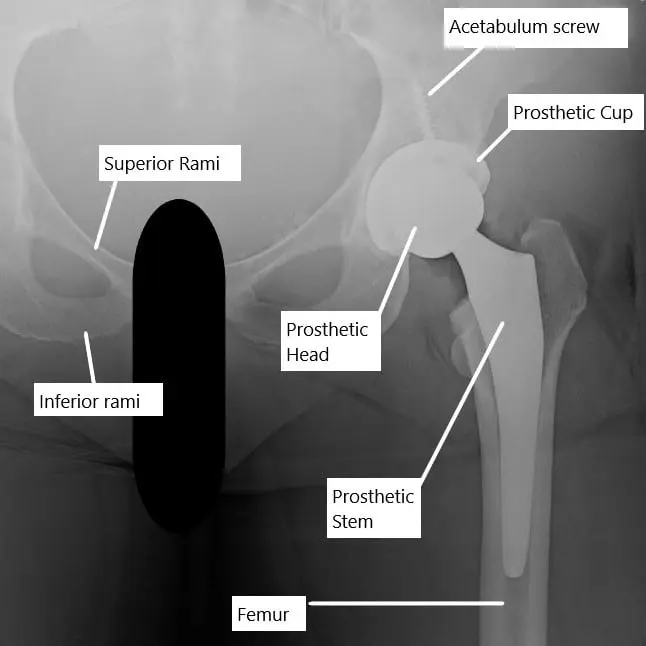

The hip is a ball-and-socket joint formed by the femoral head (ball) and the acetabulum (socket) of the pelvis. Both surfaces are covered by smooth cartilage, which allows pain-free motion. During total hip replacement, damaged cartilage and bone are replaced with prosthetic components: a metal or ceramic ball attached to a metal stem fitted into the femur, and a metal cup lined with plastic, ceramic, or metal in the acetabulum. These components restore joint function, reduce friction, and relieve arthritic pain.

X-ray showing a total hip replacement.

Evaluation of hip pain after replacement begins with X-rays to assess implant position, loosening, or bone resorption. CT scans may be used to detect subtle bone loss or heterotopic ossification, while MRI can identify soft tissue injuries, bursitis, or tendon inflammation. Blood tests (e.g., ESR, CRP) and joint aspiration help rule out infection. Imaging findings guide treatment decisions, such as revision surgery for implant failure or conservative therapy for soft tissue inflammation.